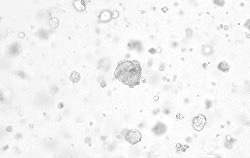

Excellent performance validated by multiple organoid cultures

Human breast cancer organoids

Human breast cancer organoids were cultured with FGF7 (Cat#: 10210-H07E), RSPO1 (Cat#: 11083-HNAS), IGF1 (Cat#: 10598-HNAE), EGF (Cat#: 50482-MNCH), NRG1 Beta 1 (Cat#: 11609-H01H), and NOG (Cat#: 50688-M02H). Image Credit: Sino Biological US Inc.

Human liver cancer organoids

Human liver cancer organoids were cultured with FGF2 (Cat#: 10014-HNAE), HGF (Cat#: 10463-HNAS), FGF7 (Cat#: 10210-H07E), EGF (Cat#: 50482-MNCH), FGF10 (Cat#: 10573-HNAE), TGFB1 (Cat#: 10804-HNAC), NOG (Cat#: 50688-M02H), and RSPO1 (Cat#: 11083-HNAS). Image Credit: Sino Biological US Inc.

Human biliary cancer organoids

Human cholangiocarcinomas organoids were cultured with FGF2 (Cat#: 10014-HNAE), HGF (Cat#: 10463-HNAS), FGF7 (Cat#: 10210-H07E), EGF (Cat#: 50482-MNCH), FGF10 (Cat#: 10573-HNAE), NOG (Cat#: 50688-M02H), and RSPO1 (Cat#: 11083-HNAS). Image Credit: Sino Biological US Inc.

Human colorectal organoids

Human colorectum organoids were cultured with RSPO1 (Cat#: 11083-HNAS), EGF (Cat#: 50482-MNCH), and NOG (Cat#: 50688-M02H). Image Credit: Sino Biological US Inc.